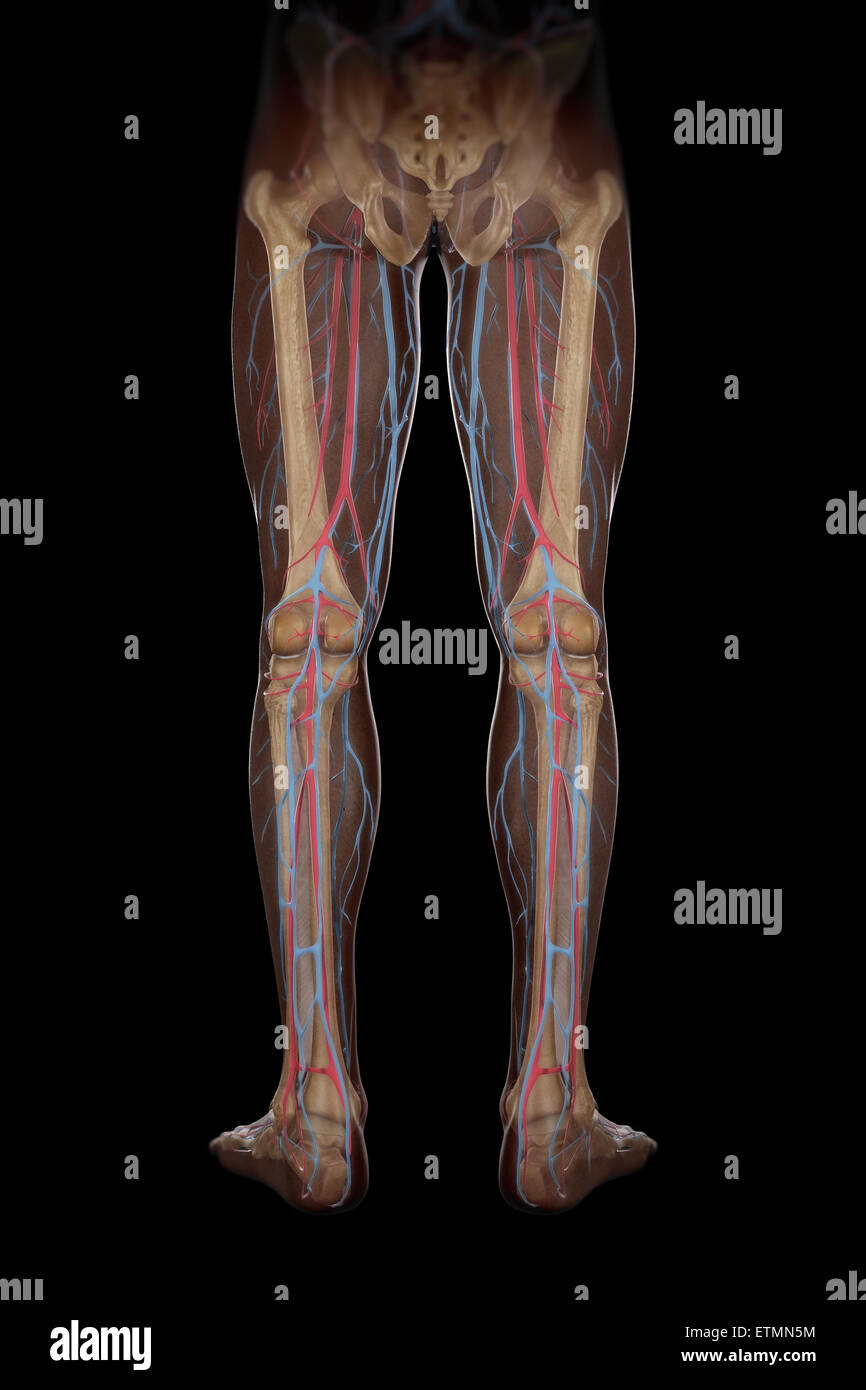

RF2KDED11–Arterielle Versorgung des vorderen und hinteren Beins über die Arteria poplitealis und ihre Zweige

RMETMN27–Darstellung der Blutversorgung und Skelett-Struktur der Unterschenkel, durch die Haut sichtbar.

RMETMNMF–Darstellung der Blutversorgung und Skelettsystem an den Unterschenkeln, durch die Haut sichtbar.

RMETMP9E–Darstellung der Blutversorgung und Skelett-Struktur der Unterschenkel, durch die Haut sichtbar.